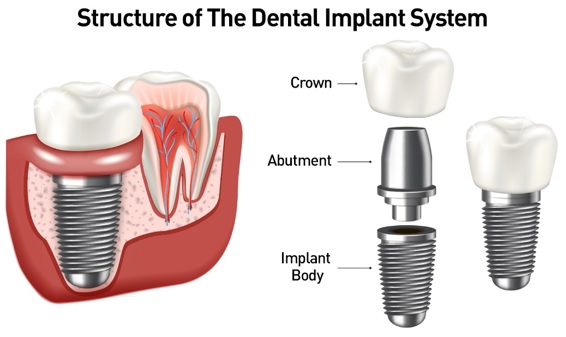

Affordable Dental Implants in Sugar Land Texas Dental implant is an artificial root, basically, that we can attach a tooth too. So, when a root is bad, we can replace the root with a dental implant and then put a crown on that tooth the way we would an actual tooth. Dental implant is a good solution to replace a tooth compared to every other option because it doesn't rely on the adjacent teeth at all. Whether it would be a bridge, which would involve crowing those adjacent teeth and connecting a tooth to the middle, or a removable appliance that connects to teeth as well. We are proud to offer a variety of procedures, from routine dental implant Sugar Land TX and wisdom teeth removal to advanced facial reconstruction and the treatment of oral pathologies. If you have any further questions about our procedures, please feel free to contact

9 Key Factors That Affect Dental Implant Pricing A single dental implant can cost somewhere in the range of $1000 to $3000. Need a full set of implants? That can set you back anywhere from $24,000 to $100,000. That's kind of like the difference between a Ford and a Ferrari. Why does dental implant pricing vary so much? Well, there are a few factors that go into the final cost of dental implants. In this video we’ll look at 9 of the biggies. 1. Preliminary work Involves things like x-rays or CT scans. our cosmetic dentist is going to have to get the lay of the land, so to speak, of your mouth before doing any work. That may in the types of scans needed and how many are needed will affect pricing. 2. The Condition of Your Mouth Do you have to get a tooth or teeth yanked out

Dental Implants & Bone Grafting after Tooth Extractions What bone grafts do we need after tooth extractions & how does it help secure dental implants? Today I’m going to review everything you need to know about this grafting procedure so you can make better decisions before your next extraction appointment. (Cut) So what is bone grafting? A bone graft is a surgical procedure that involves the transplantation of bone tissue. & We can get the transplant from our own body, cadaver bone, animal bone, or synthetic bone. It is typically associated with dental implant placement but can also be used to help support a complete or partial denture or support a deficient ridge if your getting a dental bridge done. When we extract a tooth, the bone surrounding the tooth will naturally start shrinking (resorbing) both vertically and horizontally. This can become a problem especially if you are considering getting dental implants in the

What is a sinus lift? Many patients come to our office looking for dental implants. We evaluate to see if they're a candidate. Sometimes they're not a candidate right now and need what is called a bone graft, a sinus augmentation, or a sinus lift. So the next question is always, what is a bone graft? Many times, people decline treatment because they don't fully understand what it is and have a fear because of the term, "sinus lift". To be honest, the sinus lift is probably the most successful bone grafting procedure that is done, despite the scary name. So a dental implant is a manmade root that is placed into the bone. This root is made out of titanium and is usually between three and a half millimeters to five millimeters wide. We need adequate bone in order to place the implant. We need to have at least